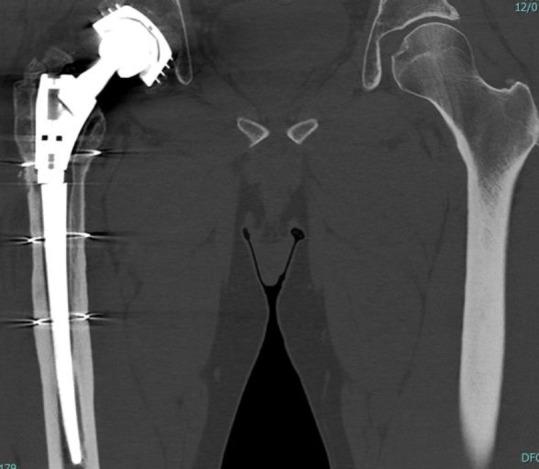

模块化牢固固定型髋关节翻修柄骨折:一例报告及文献综述

Modular Well-Fixed Hip Revision Stem Fracture: A Case Report and Literature Review.

This study presents a case of repeated prosthetic fractures in a modular hip prosthesis in a 56-year-old male patient. After the initial implantation of a modular total hip prosthesis in 2006, the patient experienced two instances of prosthetic implant fractures over seventeen years. In this study, we analyze the clinical case, explore potential underlying causes of this complication, and delve into current indications and strategies for the revision of fractured prosthesis stems. The discussion is informed by a literature review and underscores the significance of selecting appropriate revision techniques to address this challenge.

摘要

本研究报告了一例56岁男性患者模块化髋关节假体反复发生假体骨折的病例。2006年首次植入模块化全髋关节假体后,该患者在十七年中经历了两次假体植入物骨折。在本研究中,我们分析了该临床病例,探讨了这种并发症的潜在根本原因,并深入研究了目前骨折假体柄翻修的适应症和策略。讨论以文献综述为依据,并强调选择合适的翻修技术来应对这一挑战的重要性。